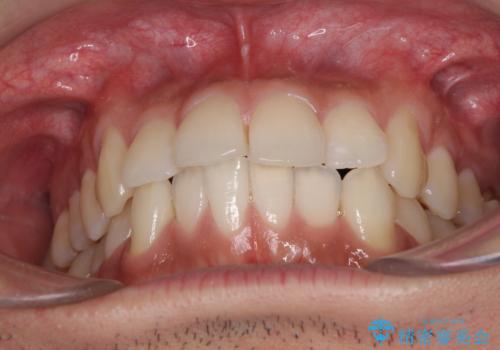

前歯のデコボコを治したい インビザライン矯正治療

- 前歯のデコボコを治したいとのことで来院された患者様です。

上下顎ともに歯列全体の後方移動とIPR(歯と歯の間を削る)によってデコボコが解消するように設計し、インビザラインにより治療を行うこととしました。

毎日22時間以上しっかりとマウスピースを装着していただいたので、スムーズに治療が進みました。歯と歯の間を削ることでうまくスペースコントロールでき、1年強で終えることができました。